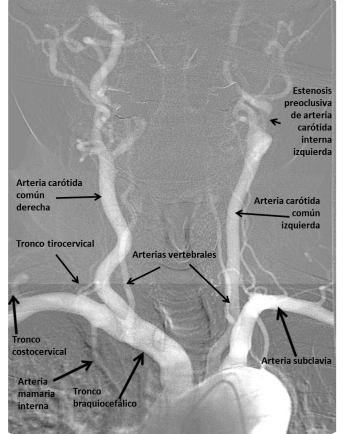

En esta entrada os presento las imágenes de arteriografía de una estenosis carotídea preoclusiva.

En la Imagen 1. podemos observar el arco aórtico y sus ramas principales (en orden): tronco braquiocefálico del que salen la arteria carótida común derecha y la arteria subclavia. La arteria carótida común se divide posteriormente en externa e interna. De la arteria subclavia sale la arteria vertebral, el tronco tirocervical, la arteria mamaria interna y el tronco costocervical. Posteriormente sale la arteria común izquieda y la arteria subclavia izquierda. En la arteria carótida común izquierda se observa un paso filiforme de contraste correspondiente a una estenosis carotídea.